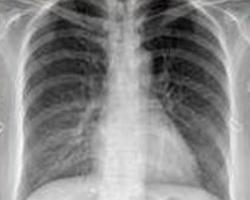

纵隔气肿(mediastinalemphysema)指气体在纵隔的结缔组织间隙内聚积 。该症多见于新生儿和婴幼儿文献报道发病率自0.04%~1%不等;成人亦不少见。成人男性发病多于女性。根据有诱发纵隔气肿的有关疾病史,有呼吸困难和胸骨后疼痛等症状,应考虑纵隔气肿的可能性;若尚有颈部和胸部皮下气肿、颈静脉充盈等体征,则应高度怀疑本症,并行胸部X线检查以明确诊断。